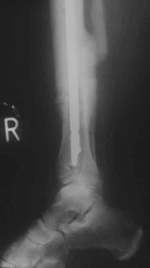

| Die offene Unterschenkelfraktur wird mit dem dynamischen Fixateur

Monotube versorgt. Durch die zusätzliche Fixierung mit Drähten

ist die Faktur nicht dynamisch stabilisiert. Trotz primärer Frakturheilung

und baldiger Belastung ist keine Knochenbildung zu erkennen. |

| Trotzdem wurde der Fixateur nach 3 Monaten entfernt. Die Patientin

belastete voll. Einen Monat später kam die Patientin mit einer

sichtbaren Fehlstellung des Unterschenkels wieder. Jetzt war auch

Callus zu sehen. |